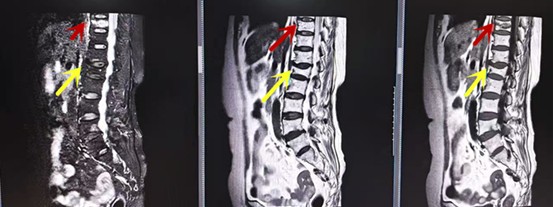

MRI利于磁場和射頻脈沖使體內(nèi)的氫原子核發(fā)生磁共振現(xiàn)象而產(chǎn)生的圖像,對軟組織的分辨率很高,對于脊髓、椎間盤、神經(jīng)、血管、韌帶、骨髓、腰部肌肉及周圍軟組織有很好的顯示效果,可以清晰的顯示腰椎間盤突出對硬膜囊、神經(jīng)根壓迫程度,以及骨折是陳舊還是新鮮,同時在脊髓病變(如脊髓損傷、髓內(nèi)出血或腫瘤)、椎管內(nèi)膿腫/血腫、椎旁肌肉軟組織病變等方面也具有優(yōu)勢,但是檢查時間較長,部分患者可能因體內(nèi)金屬植入物(如心臟起搏器、人工耳蝸等)而無法進行檢查。

箭頭提示腰椎管內(nèi)腫瘤

紅色箭頭提示新鮮骨折,黃色箭頭提示陳舊性骨折